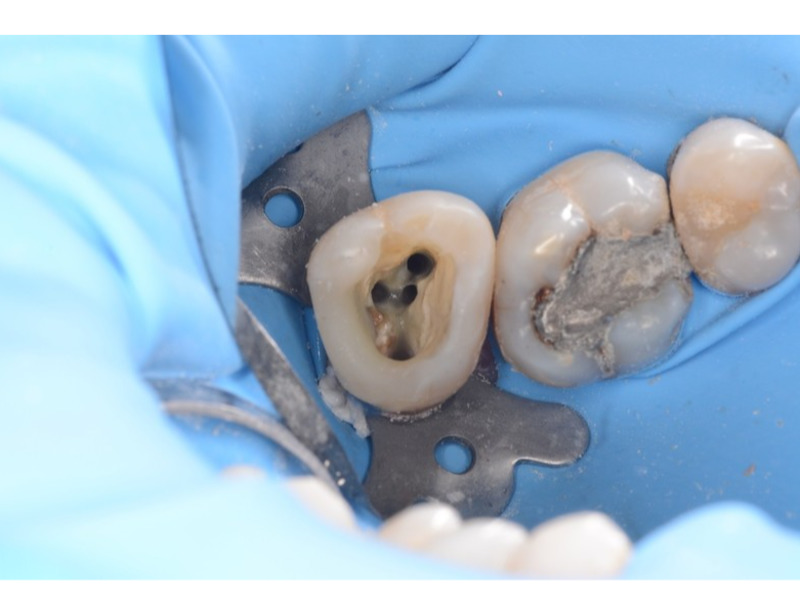

• Komplikovaná preendodontická dostavba, kofferdam

• Hledání vstupů a sondáž kořenových kanálků